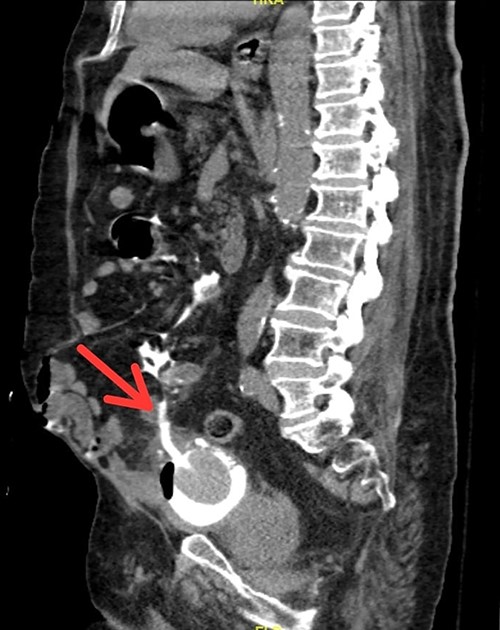

Our patient is an 80-year-old male known case of ischemic heart disease, hypertension and diabetes. He has been following with urology since 2010 as he was having recurrent urinary tract infections and high post-void residuals. A urodynamic study was done for the patient and was diagnosed with atonic bladder due to diabetic cystopathy. The patient has been on a Foley catheter since his diagnosis was established with catheter exchange in the urology clinic every 6–8 weeks. In 3 weeks from the last catheter exchange, the urology on-call team was called to the emergency room as the patient presented with a change in mental status, lower abdominal pain for 3 days which have worsened on the day of admission and no urine output from the catheter for 24 h. The pain was generalized, severe and dull in nature. The patient reported vomiting three times and has been having decreased oral intake for 2 days. Fever, chills or rigors were denied. No history of trauma or urine leakage per urethra. His abdomen was distended, and rigidity was noted in the suprapubic area. Upon flushing the catheter with normal saline, minimal output was noted with aspiration. All vital signs were within normal. He had a history of undergoing laparotomy 2 years prior to his presentation due to bowel ischemia. Bedside ultrasound was showing unclear margins of the bladder. Computerized tomography (CT) was done and showed multiple urinary bladder diverticula and the Foley catheter tip was traversing the dome of the urinary bladder and located in the intra-peritoneum (Fig. 1). The patient was taken to the operating room where laparotomy was done. Intraoperatively, adhesiolysis was carried out with difficulty in identifying the bladder. Bladder’s dome was seen where the tip of the Foley catheter was eroding through the bladder dome. A figure-of-eight stitch was taken using Vicryl suture. A leak test was done with no evidence of leakage. A new open tip catheter was inserted per urethra to prevent the catheter tip from eroding again through the bladder wall.

Sagittal view of CT scan showing Foley catheter protruding into peritoneal cavity.